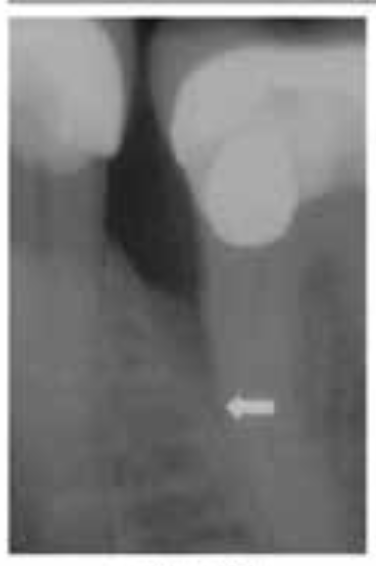

🦷 X-ray 비교

BEFORE

AFTERX-ray 상으로 명확하게 보이는 뼈 재생 효과

1Patient 1: 8년 장기 추적 케이스

치료 시작 전 상태

뼈 재생 진행 확인

재생된 뼈의 장기 유지 확인

✨ 핵심 포인트: Emdogain 치료 후 3년에 걸쳐 점진적으로 재생된 치조골이 8년이 지난 후에도 안정적으로 유지되고 있음을 확인할 수 있습니다. 이는 Emdogain의 장기적인 효과와 안정성을 보여주는 중요한 임상 증거입니다.